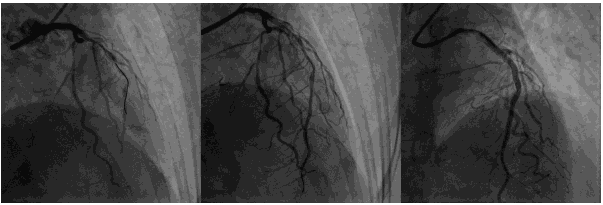

第一次冠脉造影

造影时间:2015年07月17日。

造影结果1:右冠弥漫性病变,近中段90%狭窄。

造影结果2: 左主干正常,前降支弥漫性斑块,近中段80%~90%狭窄,回旋支中远段80%~90%狭窄。

![]()

造影结论及应对策略:本病例行冠脉造影发现: 右冠弥漫性病变,近中段90%狭窄。左主干正常,前降支弥漫性斑块,近中段80%~90%狭窄,回旋支中远段80%~90%狭窄。家属要求PCI治疗。本次先开通右冠,择期开通左冠。